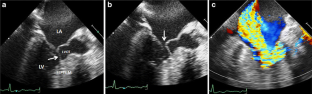

Fig. 1